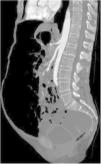

A previously healthy 65-year-old woman presented with symptoms of colicky abdominal pain and intense bloating, nausea and vomiting, and 8kg weight loss within the past 12 months. Her vital signs were stable, and she had no signs of peritoneal irritation. Abdominal angiotomography identified diffuse pneumatosis intestinalis with a predominantly cystic pattern, as well as abundant intraperitoneal free air, free fluid in the pelvic cavity, and no alterations in the mesenteric vasculature (figs. 1-3). Her laboratory test results ruled out gastrointestinal, infectious, oncologic, rheumatologic, pulmonary, and pharmacologic causes that would explain the tomographic findings. The patient received treatment based on metronidazole, probiotics, and prucalopride, and presented with partial symptom improvement, but no remission of the radiologic findings after 6 months of follow-up. The present case illustrates the fact that not all patients with pneumatosis intestinalis or pneumoperitoneum should be managed surgically. Pneumatosis cystoides intestinalis is a rare radiologic finding of unknown etiology. The differential diagnosis includes numerous causes, particularly intestinal ischemia. Treatment consists of antibiotics, prokinetics, hyperbaric oxygen, or endoscopic lesion resection, with varying results. Its clinical progression tends to be chronic and benign.